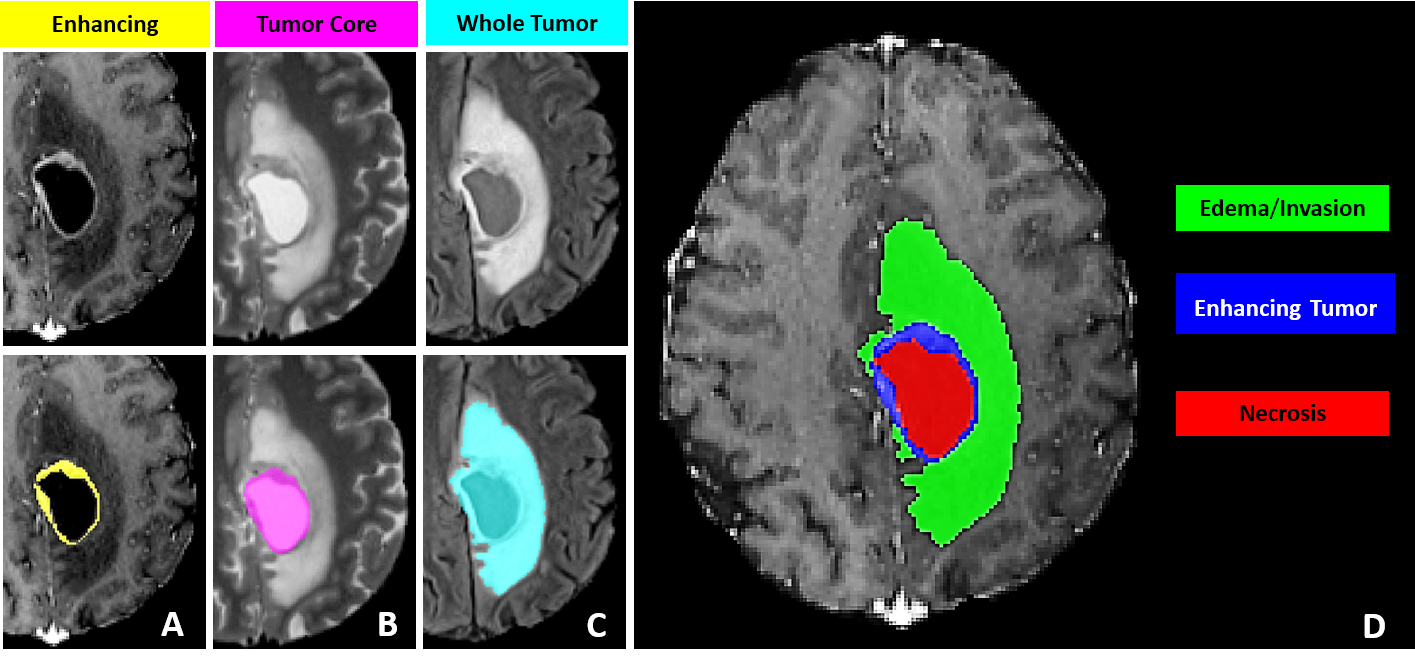

Building upon observations during all previous BraTS instances, we note some common errors in the automated segmentations. The most typical such errors observed are:

1. 1.

The choroid plexus and areas of T1 bright blood products (when they can be discriminated by comparing with the pre contrast T1 images), have erroneously been labelled as ED (Fig. 2(a)).

2. 2.

Vessels within the peritumoral T2 FLAIR edematous area, have been marked as ET (Fig. 2(b)).

3. 3.

Vessels within the peritumoral T2 FLAIR edematous area, have been marked as ED (Fig. 2(c)).

4. 4.

Periventricular white matter hyperintensities being confused and segmented as tumor/peritumoral regions (Fig. 2(d)).

Refer to caption

(a) Choroid plexus erroneously marked as ED.

(b) Vessels in ED marked at ET.

(c) Vessels in ED

(d) Periventricular white matter hyperintensities. Figure taken from [41].

Figure 2: Common errors expected from the automatic segmentations.